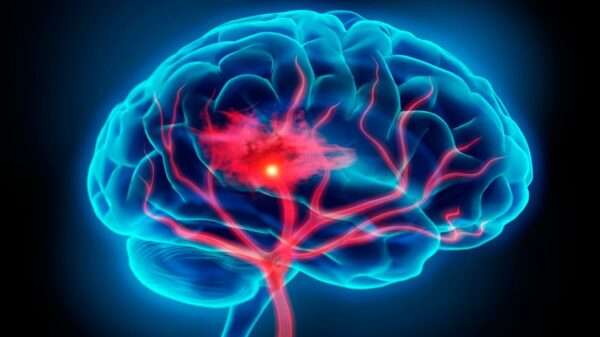

Aneurisma intracraneal

Los aneurismas saculares, comúnmente conocidos como aneurismas "berry", son dilataciones anormales en la pared de las arterias que suelen presentarse en las bifurcaciones arteriales. Esta predilección por las bifurcaciones se…